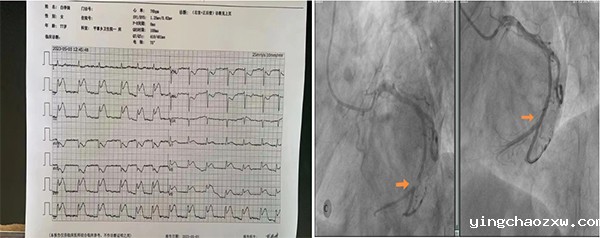

据悉,患者为女性,现年77岁,因“胸痛2小时”到新利官网登录平掌分院就诊,分院值班医师立即为患者实施心电图检查,并将患者心电图上传至总医院远程心电诊断中心。经总医院远程心电诊断中心专家审慎认真诊断,明确患者患有急性下壁+正后壁心肌梗死。患者病情万分危急,如不及时予以救治,将会引起心源性休克、恶性心律失常、心力衰竭、心肌梗塞综合征等,重则危及患者生命。“时间就是心肌,时间就是生命!”平掌分院医疗团队立即联系总医院心血管内科专家团队,共同分析讨论患者病情,考虑到平掌乡距离新平县城最为遥远(到县城需4小时余崎岖山路),若是直接转运,患者极有可能因路途遥远耗时长,在转运途中死亡。因此,总医院心血管内科专家团队与平掌分院医疗团队一致认为:就地抢救并及时溶栓后转运到总医院北院区实施PCI手术治疗是挽救患者生命的最佳治疗方案。鉴于总医院曾下派心血管内科技术骨干对平掌分院医护人员开展过溶栓治疗培训,该院医务人员具备扎实的溶栓理论知识,即使没有开展溶栓治疗的实战经验,也可在总医院心血管内科专家团队的远程指导下为患者实施溶栓治疗。于是,决定以总医院心血管内科专家团队远程指导、平掌分院医疗团队具体实施的方式为患者开展溶栓治疗,实现总医院、分院上下联动,团结协作,无缝对接。总医院心血管内科专家团队的远程支持让平掌分院医疗团队备受鼓舞,以许艳红医师和李芳护士长(原总医院心血管内科护士长)为首的平掌分院医疗团队不惧挑战,全力以赴,本着“患者至上,生命至上”的从医理念,在充分做好溶栓前评估、筛查的前提下,为患者实施溶栓治疗,成功开展了分院史上首例溶栓治疗。溶栓1小时后,患者胸痛明显缓解,复查心电图提示:心电图上ST段明显回落,病变血管溶栓再通,将患者上转至总医院北院区实施急诊PCI手术治疗的时机已经成熟。经患者家属同意后,由平掌分院120负责护送患者至总医院北院区实施急诊PCI手术治疗。途中,平掌分院负责护送患者的医护人员与总医院心血管内科专家团队保持密切联系,对患者进行严密监护,确保患者生命安全。20:10,患者被送至总医院北院区心血管内科介入导管室。心血管内科介入团队立即为患者实施PCI手术治疗,通过冠状动脉造影发现,得益于平掌分院对患者及时开展溶栓治疗,患者冠状动脉回旋支远段已由完全闭塞改善为次全闭塞,为溶栓再通。术中在患者冠状动脉回旋支远段成功植入1枚支架后,患者病情迅速好转,术后转入CCU(冠心病重症监护病房)进一步进行治疗。目前,患者病情稳定、恢复良好,患者及家属对本次高质量的抢救非常满意,并向所有参与本次抢救的医务人员致以最衷心的感谢!